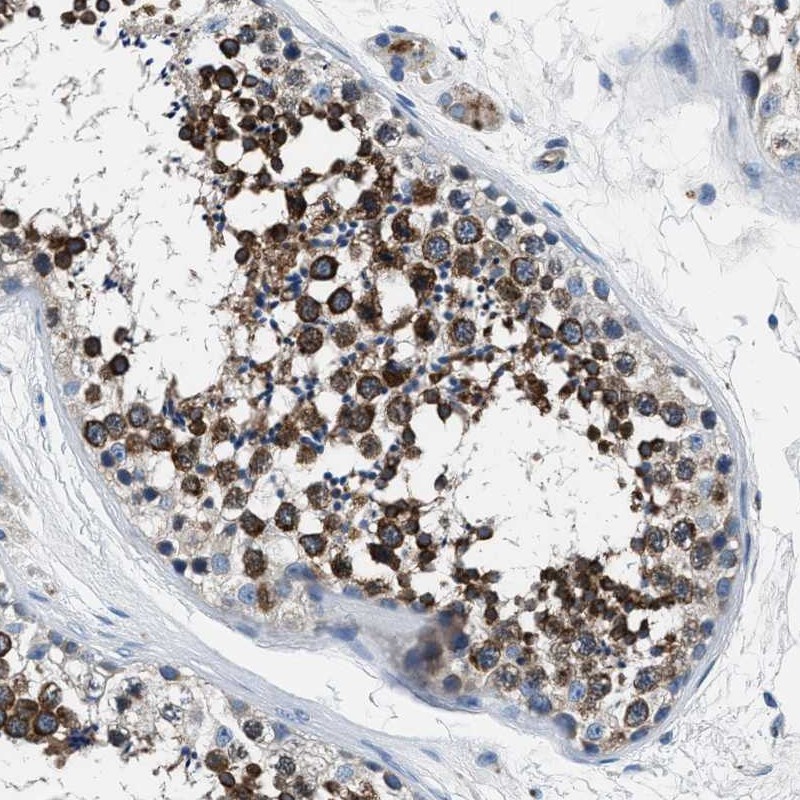

Immunohistochemical staining of human testis shows strong cytoplasmic positivity in cells in seminiferus ducts.